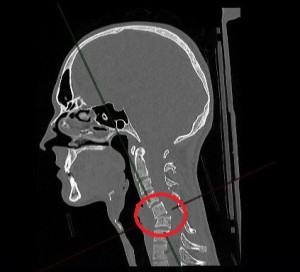

Зона перелома выделена красным цветом

Зона перелома выделена красным цветом и Перелом поперечного отростка, корня дужки и дуги пятого шейного позвонка – выделены стрелками

В ходе диагностики была выявлена тяжелая комплексная травма шейного отдела позвоночника. Врачи обнаружили множественные переломы пятого и шестого шейных позвонков, вывих пятого позвонка, разрыв межпозвонкового диска с образованием грыжи, сдавливающей спинной мозг.